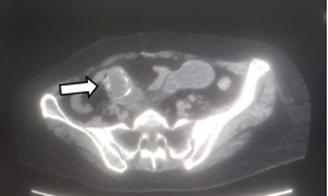

Figura 1. Cuatro formas de língulas mandibulares. Truncada (A), triangular (B), nodular (C) y asimilada (D) (8).

Figura 2. Formas de la língula en mandíbulas adultas secas. Truncada (A), presenta una forma triangular cortada en su vértice. Triangular (B), con vértice dirigido hacia el cóndilo mandibular. Nodular (C). Asimilada (D), no se evidencia la prominencia ósea lingular (8, 9).